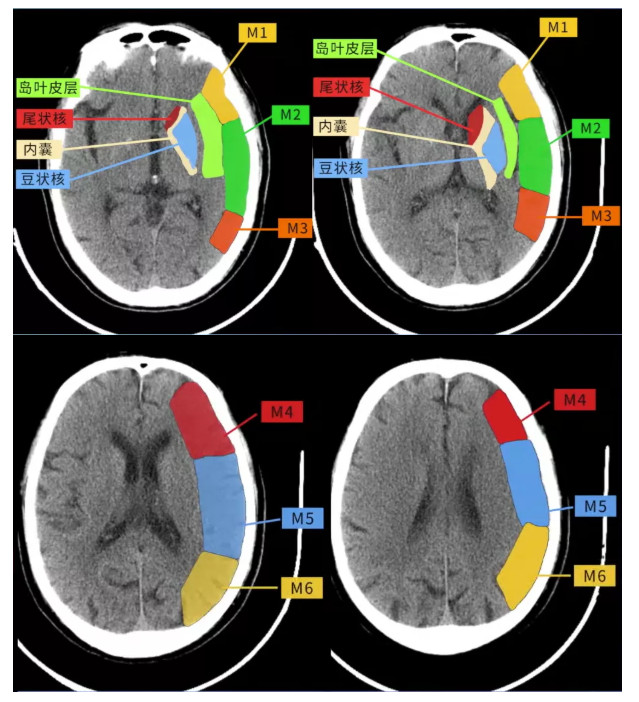

大脑中动脉(middle cerebral artery,MCA)供血区2个层面的10个区域:

①核团层面(即丘脑和纹状体平面),分为M1、M2、M3、岛叶、豆状核、尾状核和内囊后肢7个区域;

②核团以上层面(在核团水平上2cm),包括M4、M5 和M6。

两者的界限为尾状核头部:

任何位于尾状核及其以下层面的缺血性改变为核团层面,在尾状核头部层面以上的缺血性改变为核团上层面。

各区域都为1分。评分时从10分中减去存在相应的区域数目,10分代表CT平扫正常,0分表示MCA供血区广泛缺血。